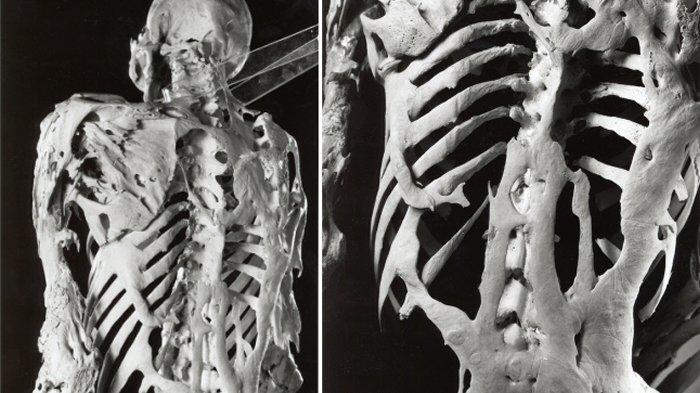

Kas dokusunun kemikleşmesi olarak özetlenebilir.Fibrodysplasia ossificans progresif (FOP) olarak da bilinir. Nadir görülen bir hastalıktır ve genetiktir. Kemikleşmeyen vücut kaslarına örnek olarak kalp kasları, dil, diyafram, düz ve göz kaslarını örnek verebiliriz.

Bu hastalık kişinin yaşamsal fonksiyonu için gerekli hareketleri kısıtlamaktadır. Kaslaşan kemiklere müdahale halinde kemikleşme hızının maalesef ki arttığı gözlemlenmiştir.

- Anormal derecede kemik büyümesinin vücut şeklinize yansıması.